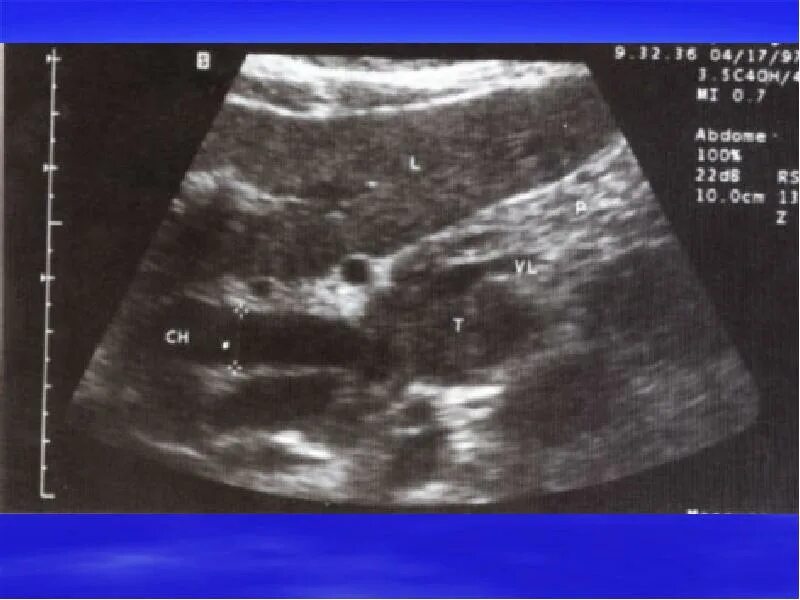

Диффузные изменения киста поджелудочной железы